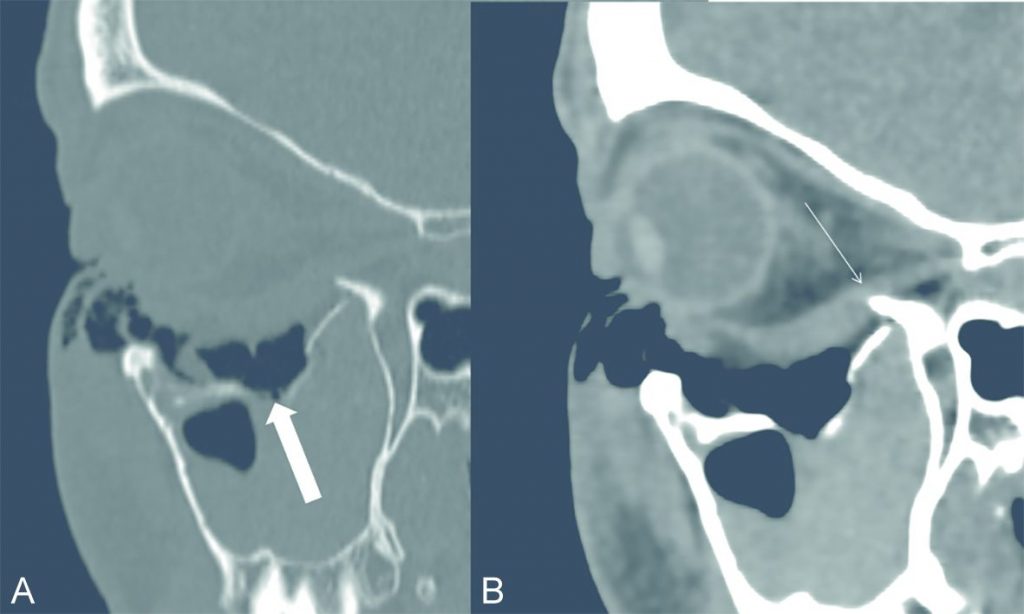

Fig. 70.1 Scanner en coupes sagittales obliques du massif facial.

(A) Filtre dur « os ». (B) Filtre tissulaire.

Fracture déplacée du plancher de l’orbite gauche avec une incarcération de graisse (flèche épaisse) et piégeage du muscle droit inférieur à la partie postérieure du plancher (flèche fine).

Source : CERF, CNEBMN, 2022.